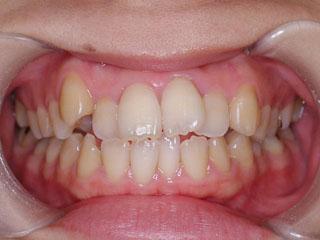

開咬と叢生が見られます。どうやら左右小臼歯間の歯は、それまでの人生でほとんど使われてこなかったようです。なので通常ですと、萌出してきたらほどなく消えてしまう前歯の先端のギザギザ(切縁結節)がそのまま残っています。概ねこのような開咬の場合は、前歯で噛もう噛もうとしているため、臼歯部を回転中心にした顎位のズレを生じている事が多いです。中心位マウントの咬合器やCPI測定で、更に大きな開咬である事が見つかります。

むりやり非抜歯で並べると、まるで前歯が噛まなくなったり、さらに顎をずらして噛む人になってしまいますので、小臼歯抜歯で対応しています。このケースでは下顎の非対称も見られるのですが、治療メカニクスが不十分であったため、正中変位の改善が達成されませんでした。しかし開咬傾向が強いケースでは、できるだけ顎間ゴムは使わない事にしています。なぜなら、そのようなメカニクスは多かれ少なかれ、顎関節のズレを生じさせると考えられるからです。今時分なら、歯科矯正用アンカースクリューのメカニクスを用いて改善しているでしょう。

使用した主な装置名:マルチブラケット装置

抜歯/非抜歯および抜歯部位:抜歯(上顎左右第一小臼歯、下顎左右第二小臼歯)

治療期間:動的処置2年6か月、経過観察3年